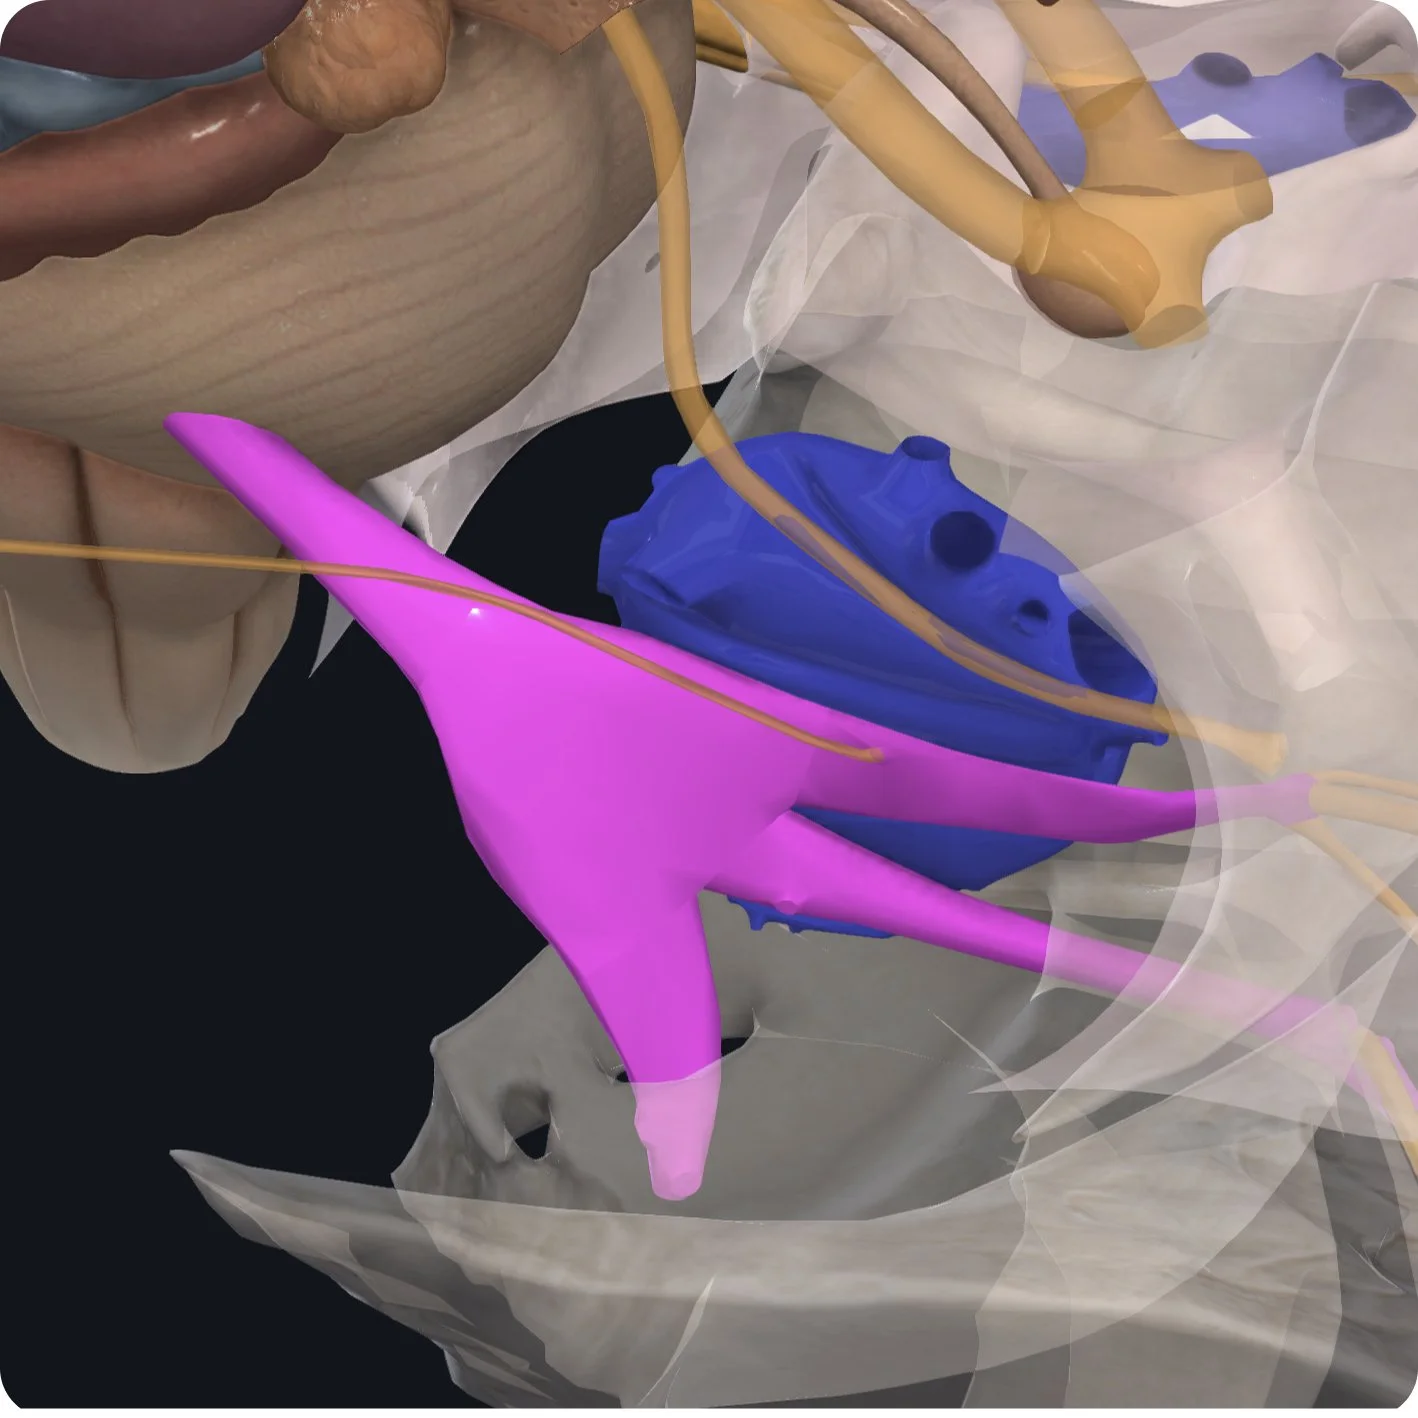

The Trigeminal nerve emerges from the brainstem on the lateral aspect of the pons.

It has two distinct roots. The sensory root is the larger of the two and carries sensory information into the brainstem.

The motor root carries motor information into the periphery.

Both roots come together at the trigeminal ganglion.

This flat, crescent-shaped structure lies on the floor of the temporal bone, between the periosteal dura and meningeal dura.

It has its own expansion of meningeal dura called meckel's cave. The unusual shape of the trigeminal ganglion is due to the large number of sensory nerve cell bodies that are within it.

The trigeminal ganglion receives information from three branches. The ophthalmic branch superiorly carries sensory information towards the forehead (V1).

The maxillary branch in the middle also carries sensory information towards the face and cheek (V2).

Inferiorly, the mandibular branch carries both motor and sensory information towards the jaw (V3).